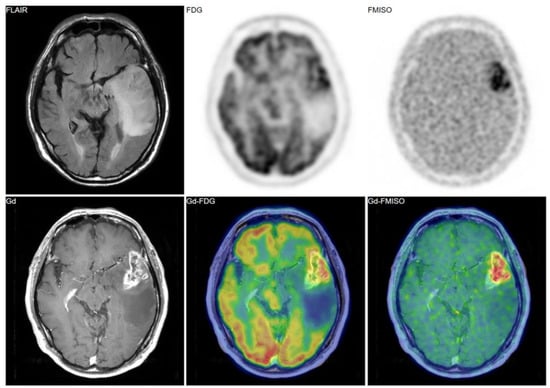

Figure 2. A 69-year-old patient had a tumor in the left temporal lobe. Fluid-attenuated inversion recovery (FLAIR) image showed high intensity, indicating the tumor and the peritumoral edema. Gadolinium enhancement, 18F-fluorodeoxyglucose (FDG) uptake, and FMISO uptake were observed in the same area. The pathological diagnosis was glioblastoma (grade IV).

Figure 3. A 38-year-old patient had a tumor in the right frontal lobe. FMISO uptake was absent despite of strong uptake of FDG. The pathological diagnosis was gangliocytoma (grade I).

Figure 4. A 69-year-old patient had a tumor in the left medial temporal lobe. Like the case in Figure 3, FMISO uptake was not observed in the tumor, whereas FDG uptake was evident. The pathological diagnosis was anaplastic astrocytoma (grade III).